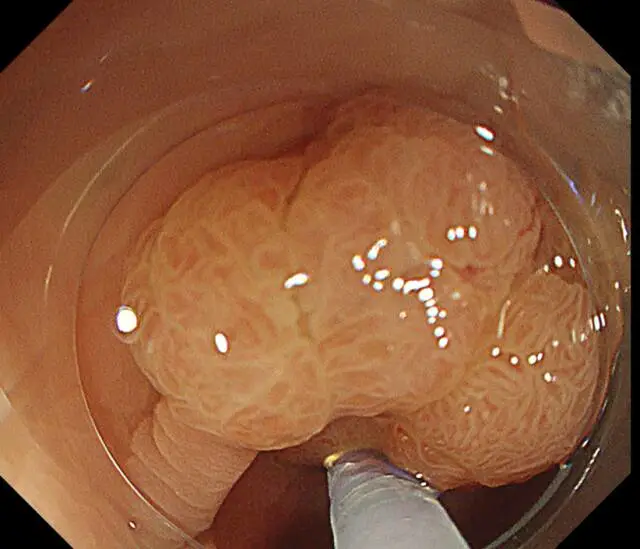

更先进的检查设备

新镜界引进国际尖端的奥林巴斯X1(CV1500)内镜系统,搭载第三代NBI窄带成像、4K超高清成像技术等,同时所有患者全部采用放大内镜放大精查,这些技术、设备可以清晰观察黏膜微血管形态、腺管开口结构,使微小的凹凸不平和组织边界更加清晰,让消化道早癌无所遁形。